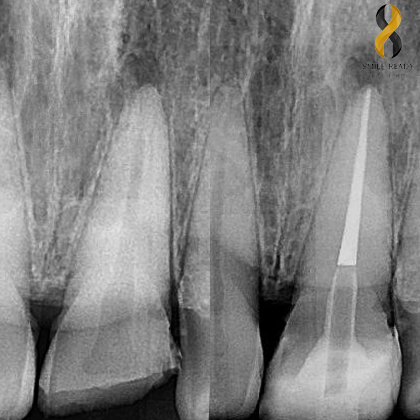

PERIAPICAL X-RAY

Is taken to evaluate the periapical area of the tooth and surrounding bone.